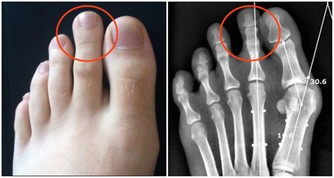

***1、指甲易斷***

中醫認為,指甲質地堅硬,是肝血充足的體現。如果指甲開始變脆,容易劈裂,則表明肝血不足、筋失所養。

***4、凹凸不平***

如果指甲並不光滑,而是有一條一條的橫紋,並且凹凸不平,這也是肝臟不好的信號,說明肝臟是存在問題的,最好去醫院檢查一下。